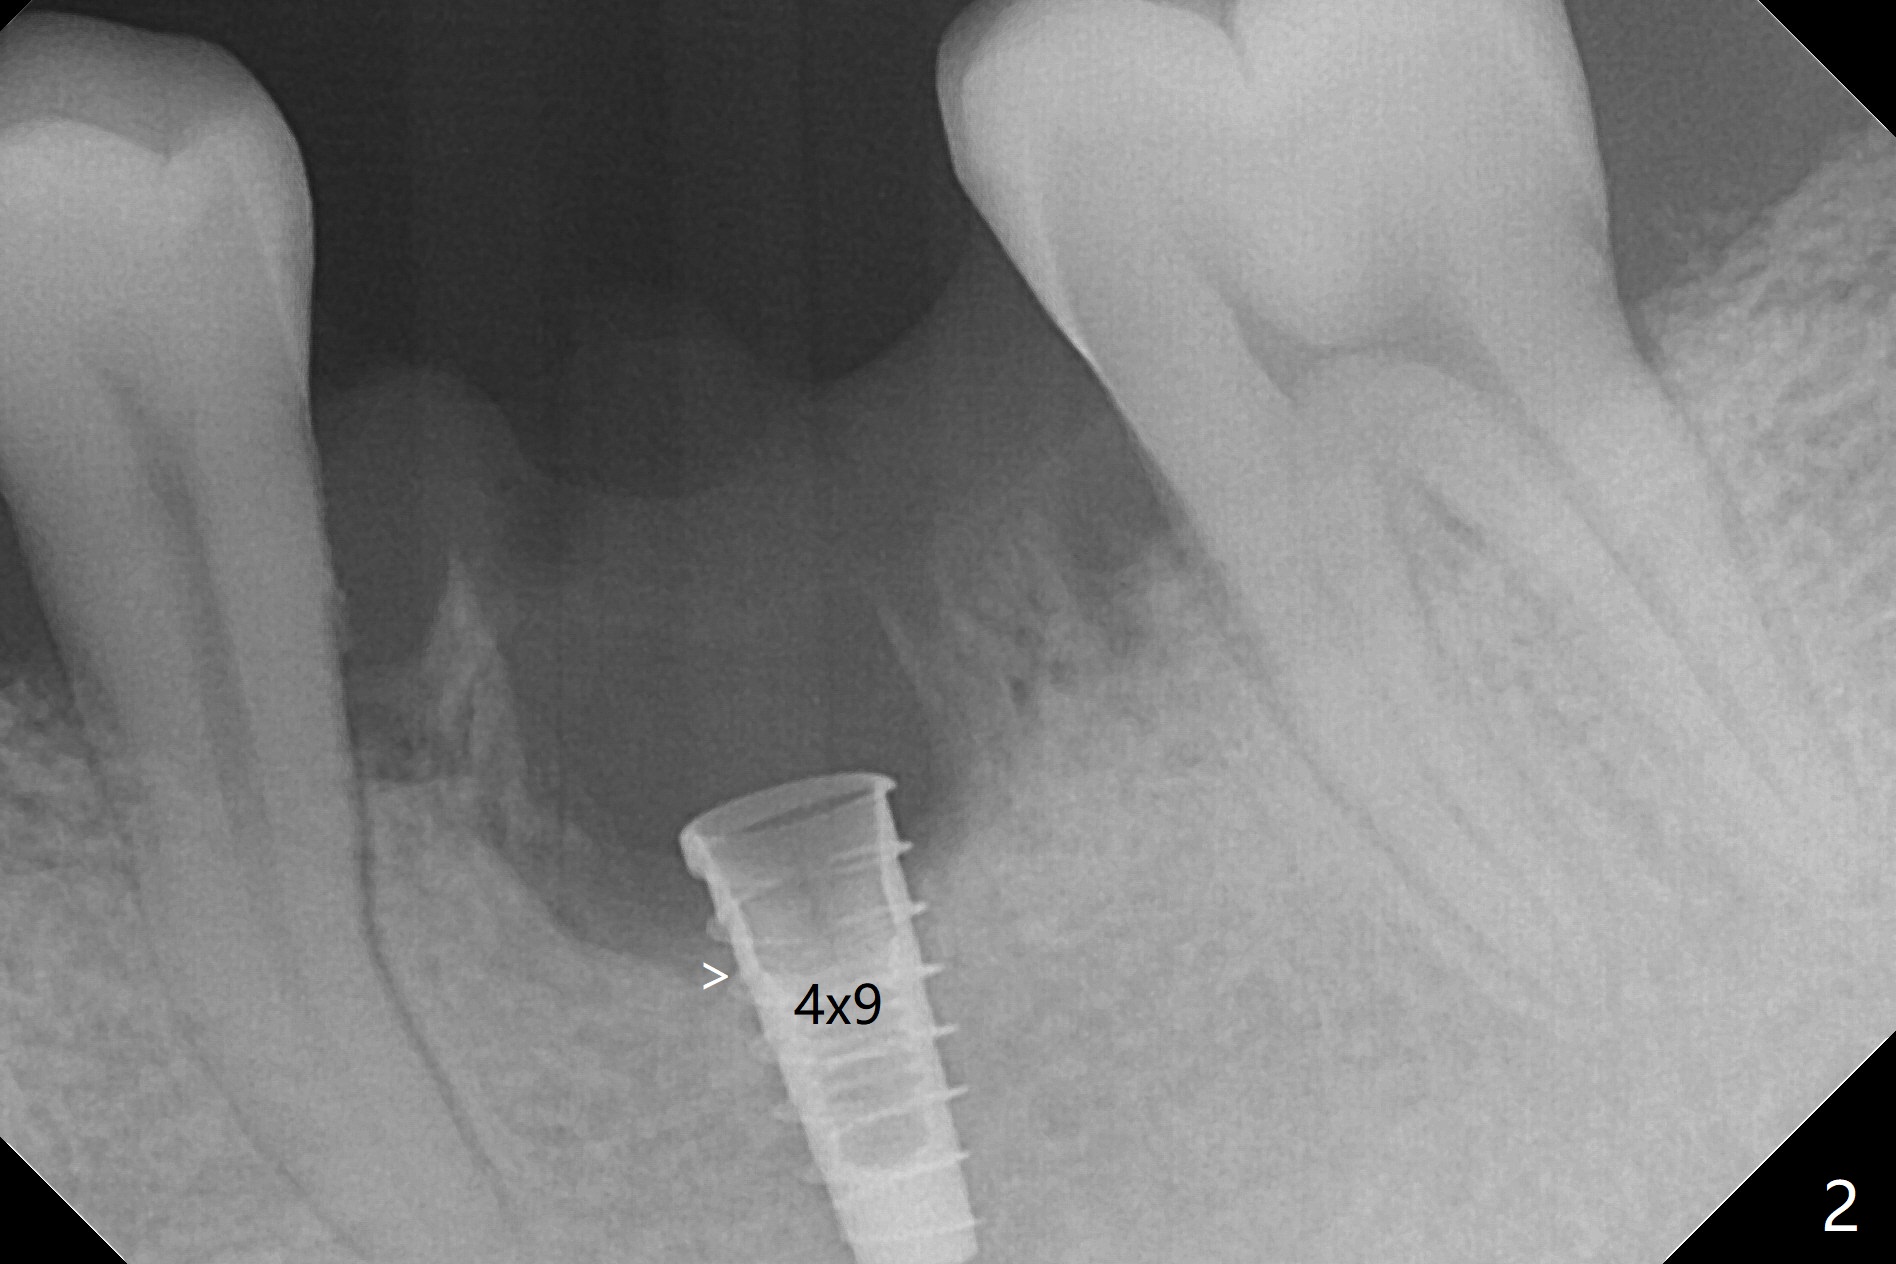

In spite of smoking reduction (1ppwk), the infection at #19, including buccal fistula (Fig.1 <) seems to be so severe that it affects pain threshold. Local anesthetics have to be added, including Bupivacaine IANB. When 4x10 mm drill is being applied, the patient feels pain. The plan is to use 4x11.5 mm drill as a final one. A 4x9 mm dummy implant is placed with 2.8 mm implant exposed (Fig.2 >), but it is subcrestal mesiodistally. Primary stability of a definitive 4.5x9 mm implant is satisfactory (Fig.3), but after initial bone graft, a 5x5.7(4) mm abutment is unable to be seated completely (<). Following 4.6 and 5.6 mm bone profile drills, the abutment remains incompletely seated (Fig.4). After fine turning, the abutment is fully seated; final round of bone graft (sticky bone) is placed mesiodistally (Fig.5 *) and buccolingually (Fig.6,7). It appears that there is tight fit between IBS implant and abutment. It is hoped that the excess bone graft with PRF is able to cover the coronal portion of the implant. If not, socket preservation should be done in this situation. In fact the implant is not placed lingual enough as compared to the design (Fig.6'). A 4.5 mm cortical drill should be used in a crown down fashion. In fact there is bone coverage coronally 5 months postop (Fig.8). Return to Prevent Molar Periimplantitis (Protocols, Table) No Deviation 12/14 Xin Wei, DDS, PhD, MS 1st edition 02/11/2020, last revision 06/30/2020